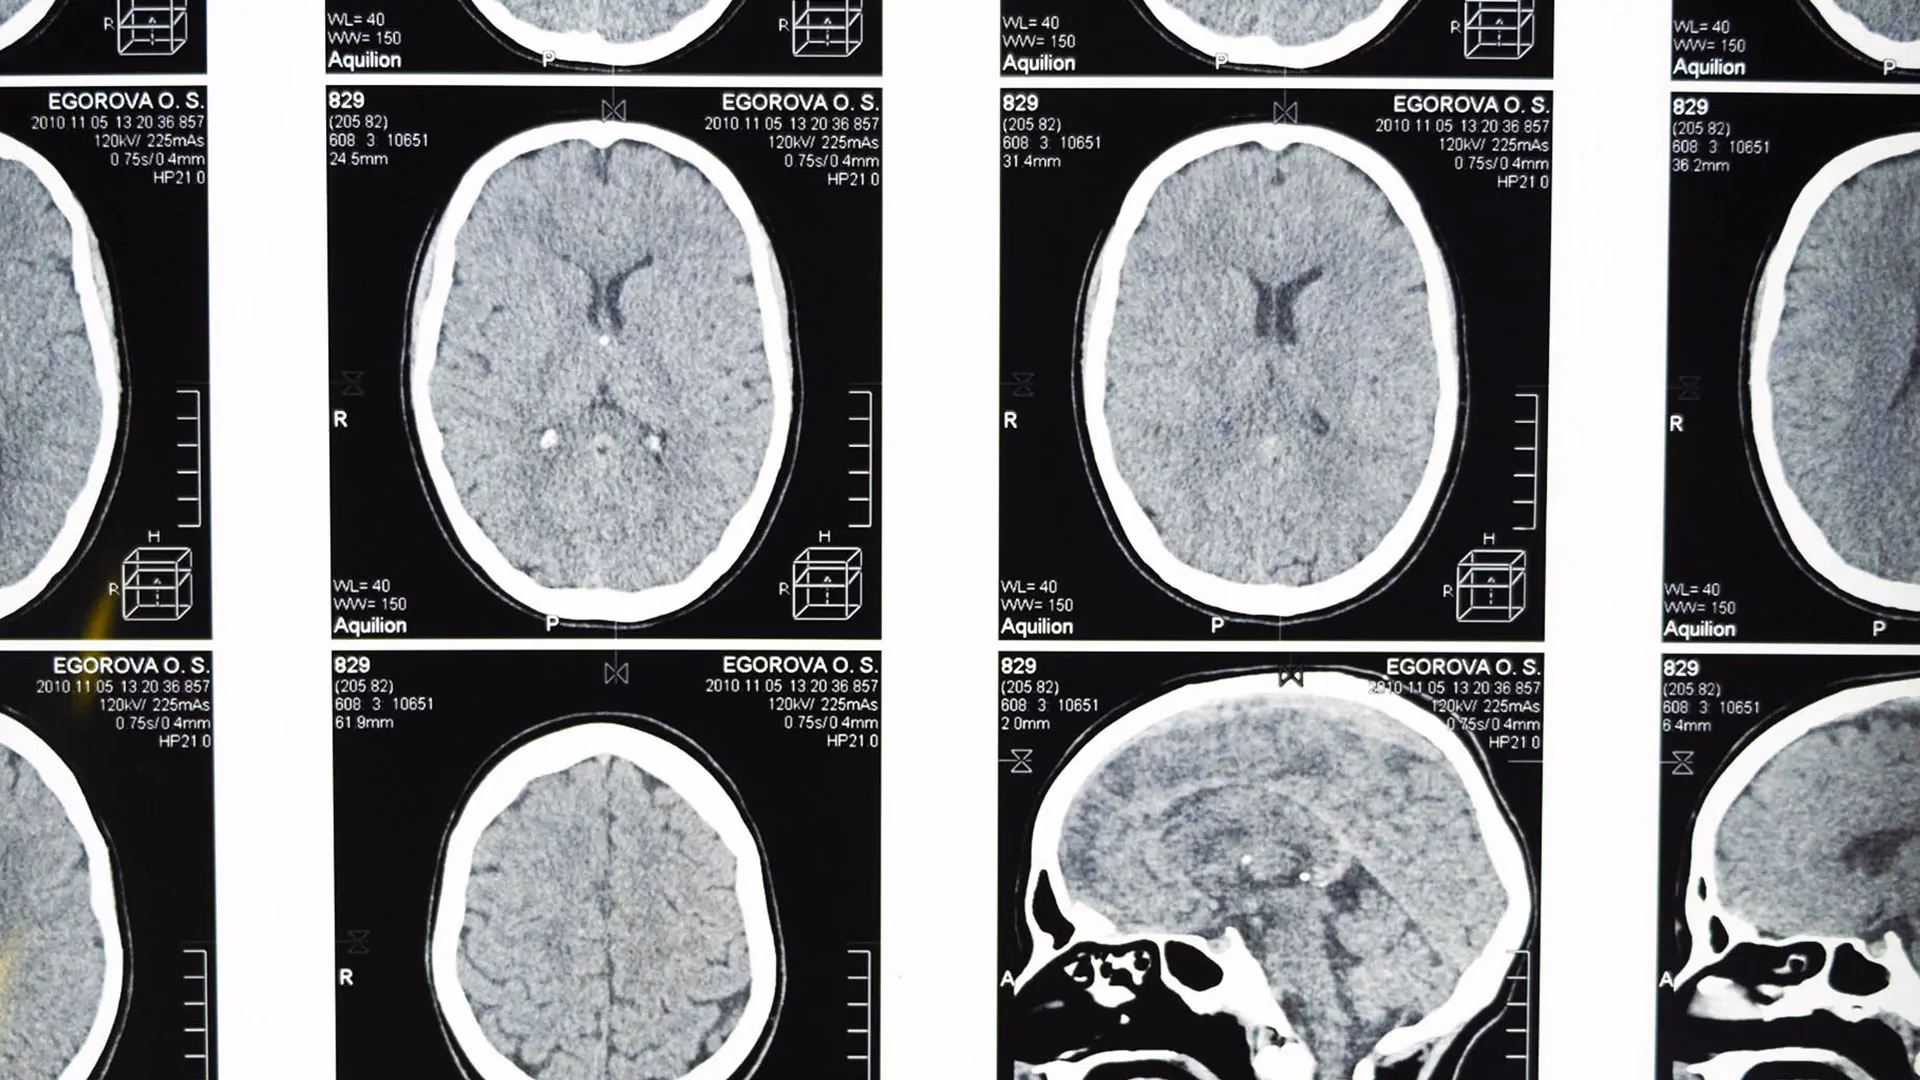

- Técnicas de Neuroimagen: En humanos, la resonancia magnética funcional (fMRI), la tomografía por emisión de positrones (PET) y la electroencefalografía (EEG) permiten observar la actividad cerebral mientras la persona realiza tareas cognitivas o conductuales.